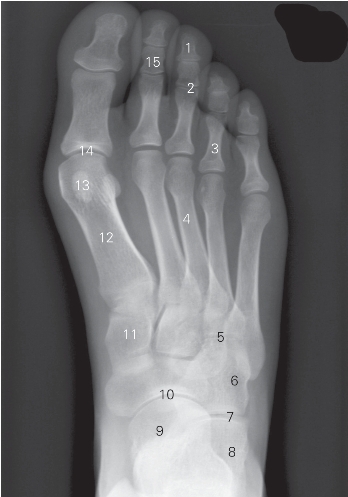

图7-9 足正位DR平片

1 远节趾骨 distal phalanx 2 趾间关节 interphalangeal joint

3 近节趾骨 proximal phalanx

4 第3跖骨 third matatarsal bone

5 跗跖关节 tarsometatarsal joint 6 骰骨 cuboid

7 跟骰关节 calcaneocuboid joint 8 跟骨 calcaneus

9 距骨 talus 10 距舟关节 talonavicular joint

11 内侧楔骨 entocuneiform 12 第1跖骨 first matatarsal bone

13 籽骨 sesamoid

14 跖趾关节 metatarsophalangeal joint 15 中节趾骨 middle phalanx